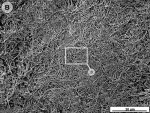

When the tooth slices with the ex vivo-grown salivary biofilm were examined under the scanning electron microscope, they were colonized by luxuriant biofilm covering the entire surface (Figure 2A, Figure 2B, Figure 2C). The biofilms appeared to be several micrometers thick. The predominant morphotypes in the biofilms were fusiform bacteria and cocci. Several regions showed co-aggregation between the two morphotypes, which is a phenomenon of mutual dependence for nutrition and growth. The salivary-derived biofilm showed characteristics typical of a naturally occurring in vivo biofilm in the mouth. The standard jet tip treatment for 3 seconds on the tooth slices with ex vivo-grown biofilm showed extensive areas of biofilm removal in comparison with the untreated control slices (Figure 2D, Figure 2E, Figure 2F). The standard jet removed 99.99% of the salivary biofilms. The orthodontic tip treatment for 3 seconds on the tooth slices appeared to clear very extensive areas of ex vivo-grown salivary biofilm (Figure 3A andFigure 3B). Biofilm removal was observed both at the crown surface and below the cementoenamel junction. The percentage of biofilm removed by the orthodontic tip was 99.84%. Observation with the naked eye indicated that treatment of in vivo biofilm with the orthodontic tip removed significant amounts of this calcified biofilm. This was evident in SEMs, which showed the presence of clearance marks (Figure 3C) caused by the bristles associated with this tip.